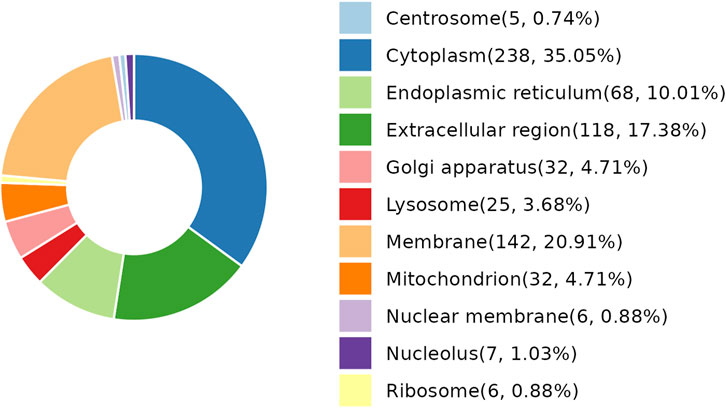

As per the results demonstrated in this study, NDSTB and DSTB samples exhibited various differentially expressed proteins (DEPs). Analysis of the subcellular localization showed that DEPs were diffusely distributed throughout the cytoplasm, extracellular region, lysosomes, Golgi apparatus, centrosome, membrane, mitochondrion, nuclear membrane, nucleolus, ribosome, and endoplasmic reticulum (Figure 4).

Figure 4. Subcellular localization analysis of DEPs. 25 DEPs were distributed in lysosomes, accounting for 3.68%. 238 DEPs were distributed in Cytoplasm, accounting for 35.05%.